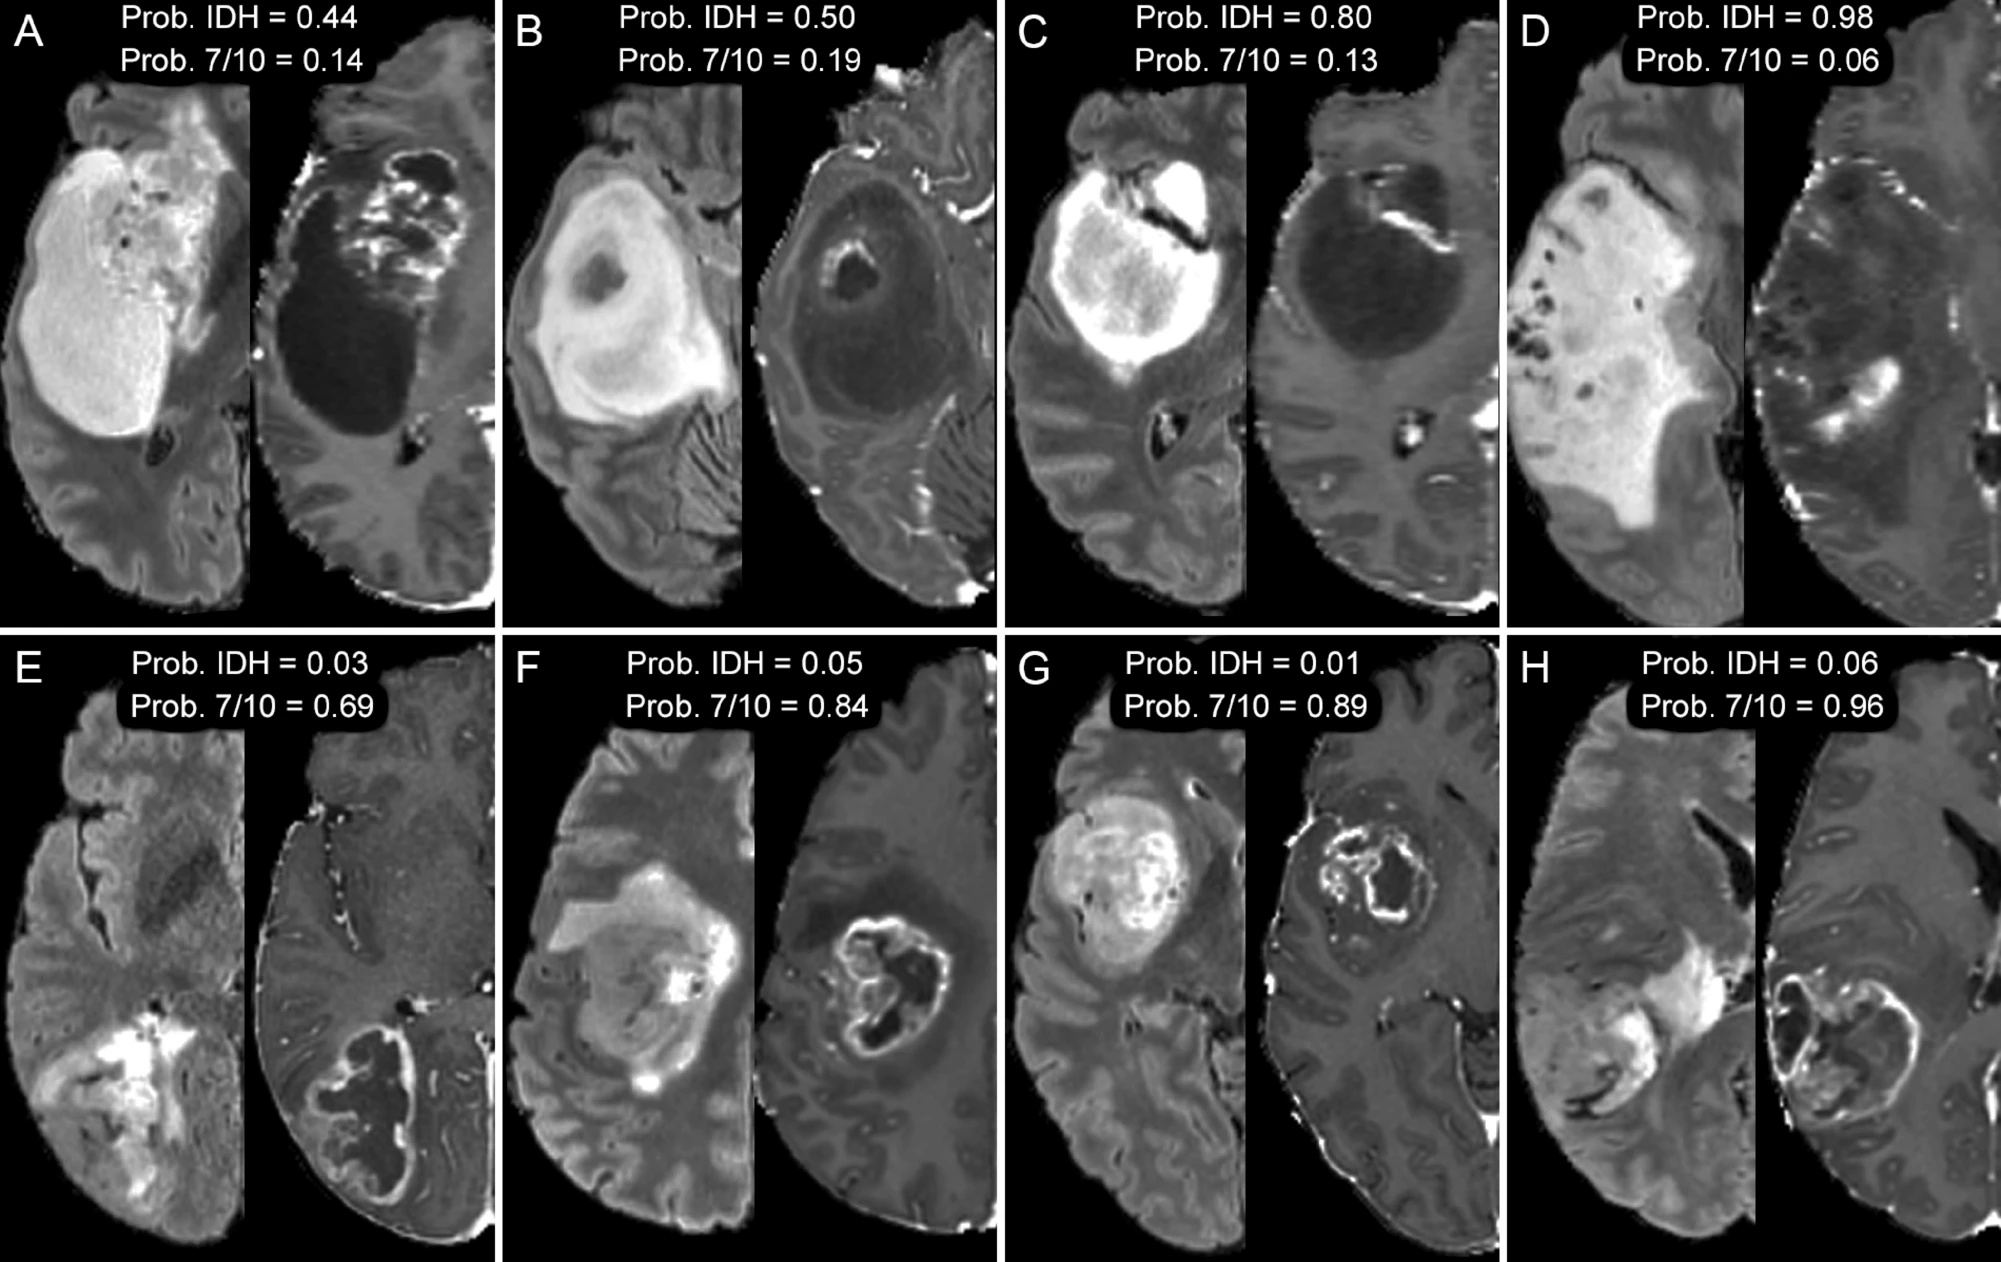

Axial MR images of glioblastomas from 8 different patients with IDH mutant (AD) and chromosome 7/10 aneuploid tumors (EH). T2-weighted FLAIR images (left) are shown beside corresponding T1-weighted postcontrast images (right). Relative probabilities of IDH mutation (Prob. IDH) and chromosome 7/10 aneuploidy (Prob. 7/10) generated from artificial intelligence models are shown for image set of images.